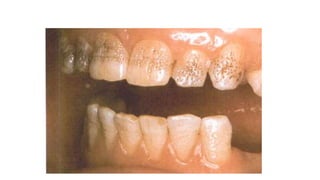

Amelogenesis imperfecta,

hypocalcified type

The soft chalky enamel was

virtually of normal thickness

and form but has chipped

away during mastication.